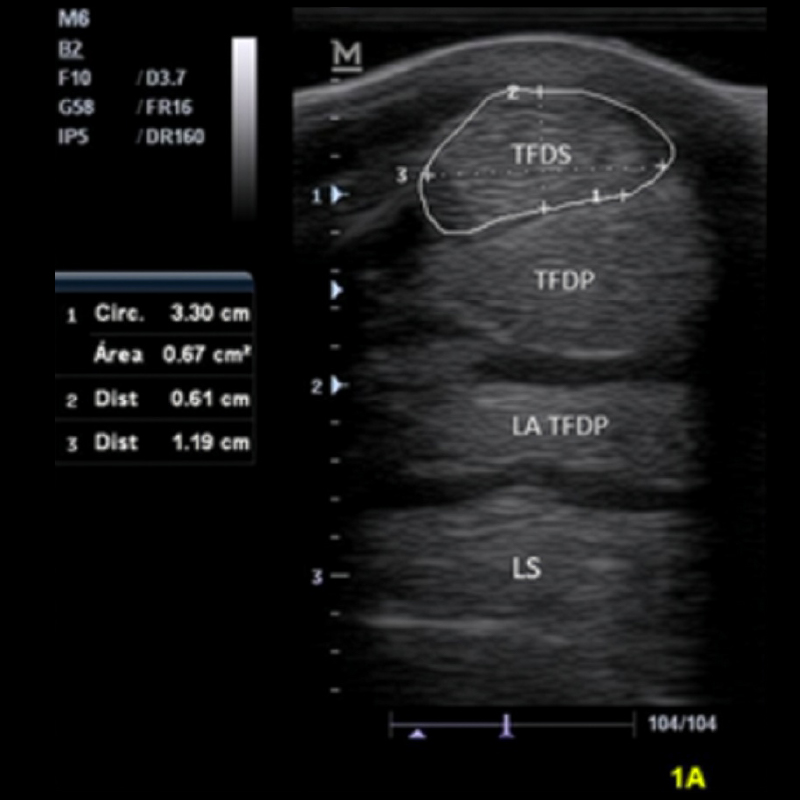

Ecografía

Asesoramiento tendino-ligamentoso

• Diferenciación entre lesiones agudas y crónicas

• Medición de riego sanguíneo

• Evaluación detallada de tendones y ligamentos

• Seguimiento fiable en rehabilitación

• Control ecográfico mensual

• Análisis de fibras, riego, ecogenicidad y evolución